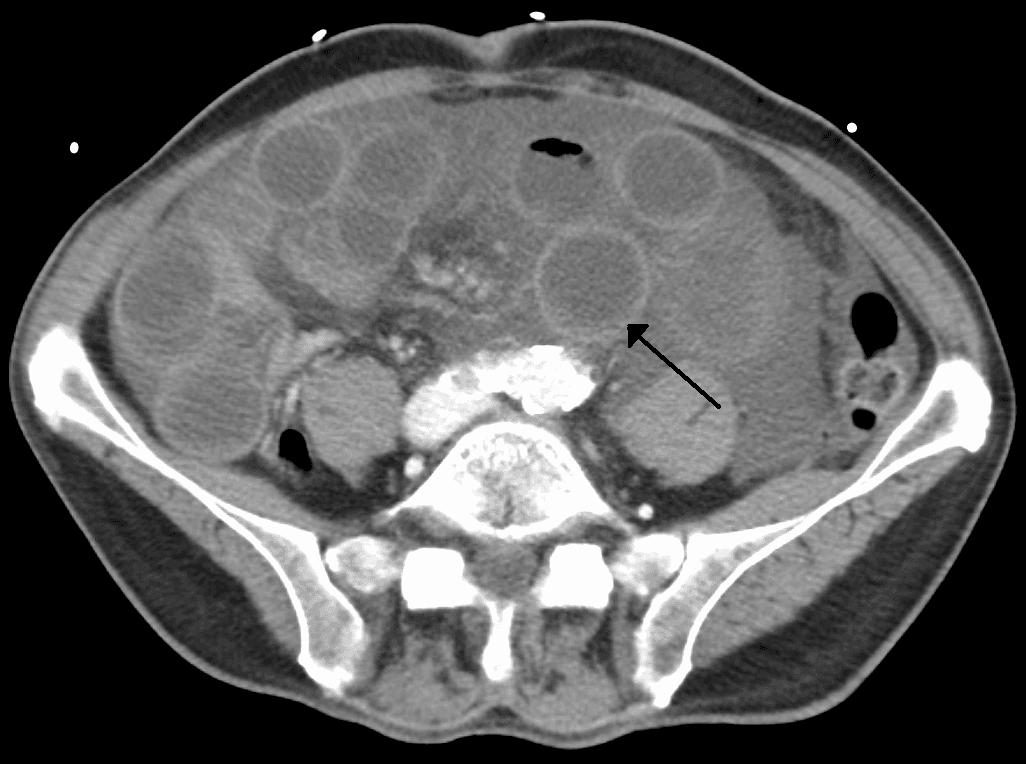

Intestinal ischemia is a medical condition in which injury to the large or small intestine occurs due to not enough blood supply. It can come on suddenly, known as acute intestinal ischemia, or gradually, known as chronic intestinal ischemia. The acute form of the disease often presents with sudden severe abdominal pain and is associated with a high risk of death. The chronic form typically presents more gradually with abdominal pain after eating, unintentional weight loss, vomiting, and fear of eating. Risk factors for acute intestinal ischemia include atrial fibrillation, heart failure, chronic kidney failure, being prone to forming blood clots, and previous myocardial infarction. There are four mechanisms by which poor blood flow occurs: a blood clot from elsewhere getting lodged in an artery, a new blood clot forming in an artery, a blood clot forming in the superior mesenteric vein, and insufficient blood flow due to low blood pressure or spasms of arteries. Chronic disease is a risk factor for acute disease. The best method of diagnosis is angiography, with computed tomography (CT) being used when that is not available. Treatment of acute ischemia may include stenting or medications to break down the clot provided at the site of obstruction by interventional radiology. Open surgery may also be used to remove or bypass the obstruction and may be required to remove any intestines that may have died. If not rapidly treated outcomes are often poor. Among those affected even with treatment the risk of death is 70% to 90%. In those with chronic disease bypass surgery is the treatment of choice. Those who have thrombosis of the vein may be treated with anticoagulation such as heparin and warfarin, with surgery used if they do not improve. Acute intestinal ischemia affects about five per hundred thousand people per year in the developed world. Chronic intestinal ischemia affects about one per hundred thousand people. Most people affected are over 60 years old. Rates are about equal in males and females of the same age.